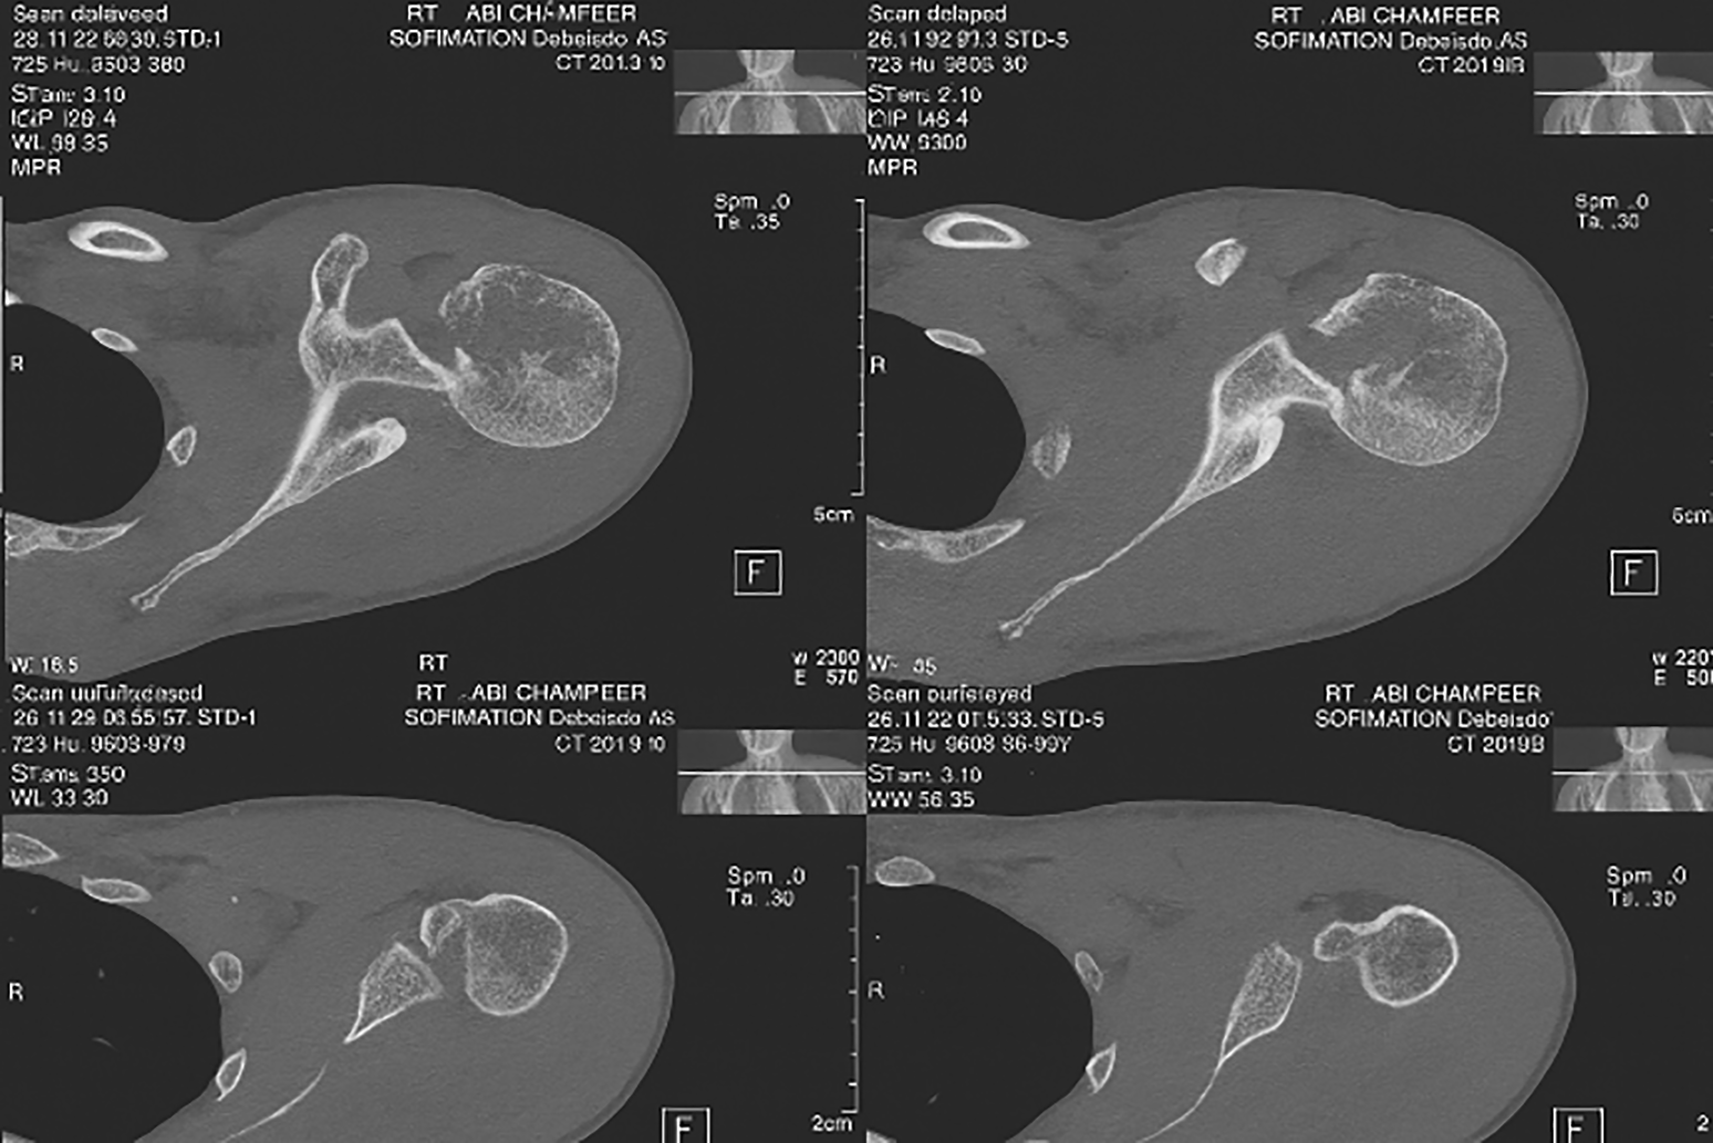

On examination, there was loss of shoulder contour with limitation of movement with a positive posterior drawer test. Radiographs showed a light-bulb appearance ( Figure 1). The CT scan showed Reverse Hillsach lesion ( Figure 2).

On examination, there was loss of external rotation movement of the shoulder. The X-rays showed a light-bulb appearance ( Figure 5). The CT scan: shows Reverse Hillsach lesion ( Figure 6).

The patient was sent for X-rays that showed a light-bulb appearance ( Figure 9). The CT scan showed the impaction of the Humeral Head in the glenoid fossa with an internally rotated Humeral Head that locks the head in situ (inside the glenoid fossa) without exiting the humeral head outside the glenoid socket ( Figure 10).

Radiology included AP, lateral, and axillary views. Computed tomography (CT) scans are required in doubtful cases. Radiological signs included a light bulb appearance, empty glenoid sign (anteroposterior, AP view), or indentation of the anterior part of the humeral head (in Lateral or Axillary view).